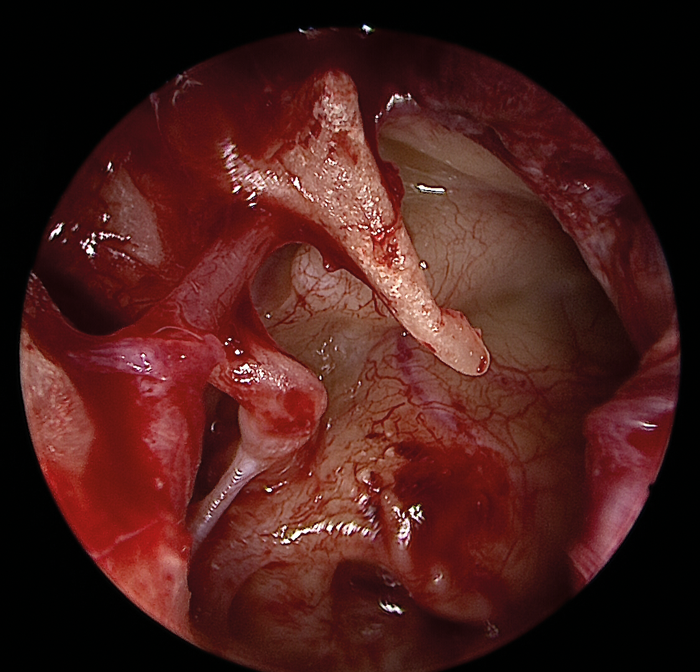

The greatest benefit of the endoscope lies in exposing previously hidden areas or blind spots such as the retrotympanum, hypotympanum, anterior mesotypanum, epitympanum and antrum (Figure 4).

Figure 4 (Top, middle and bottom): Endoscopic view of the middle ear with an intact ossicular chain.